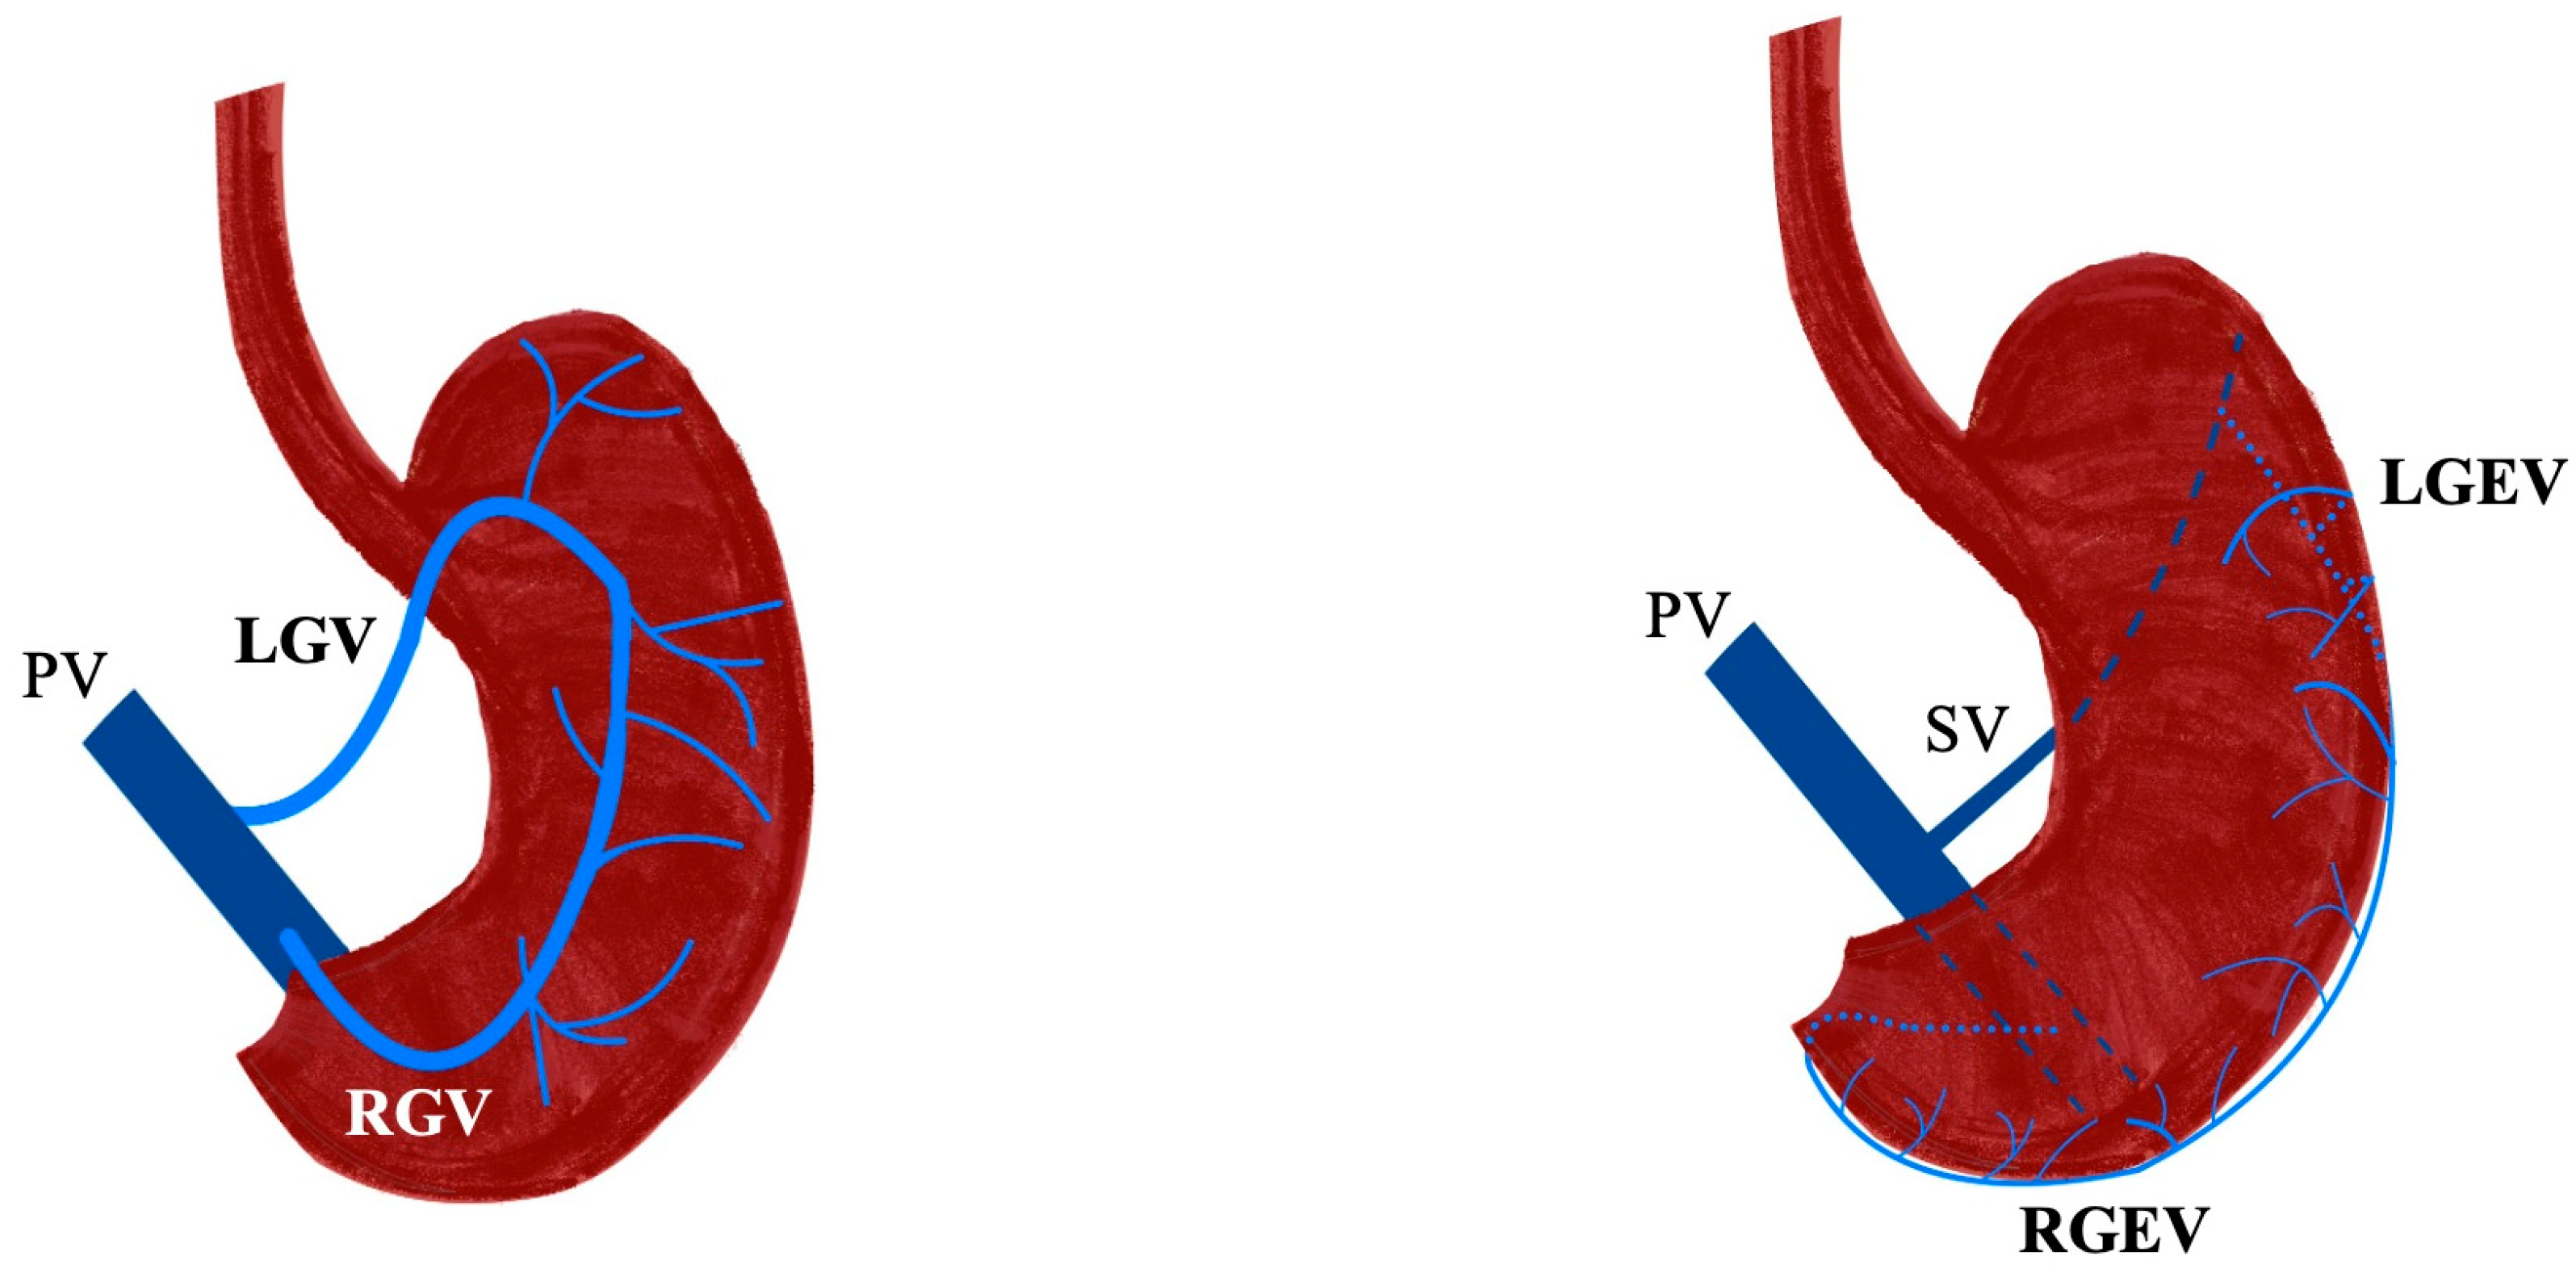

3.1. Gastric Veins

3.2. Gastroepiploic Veins